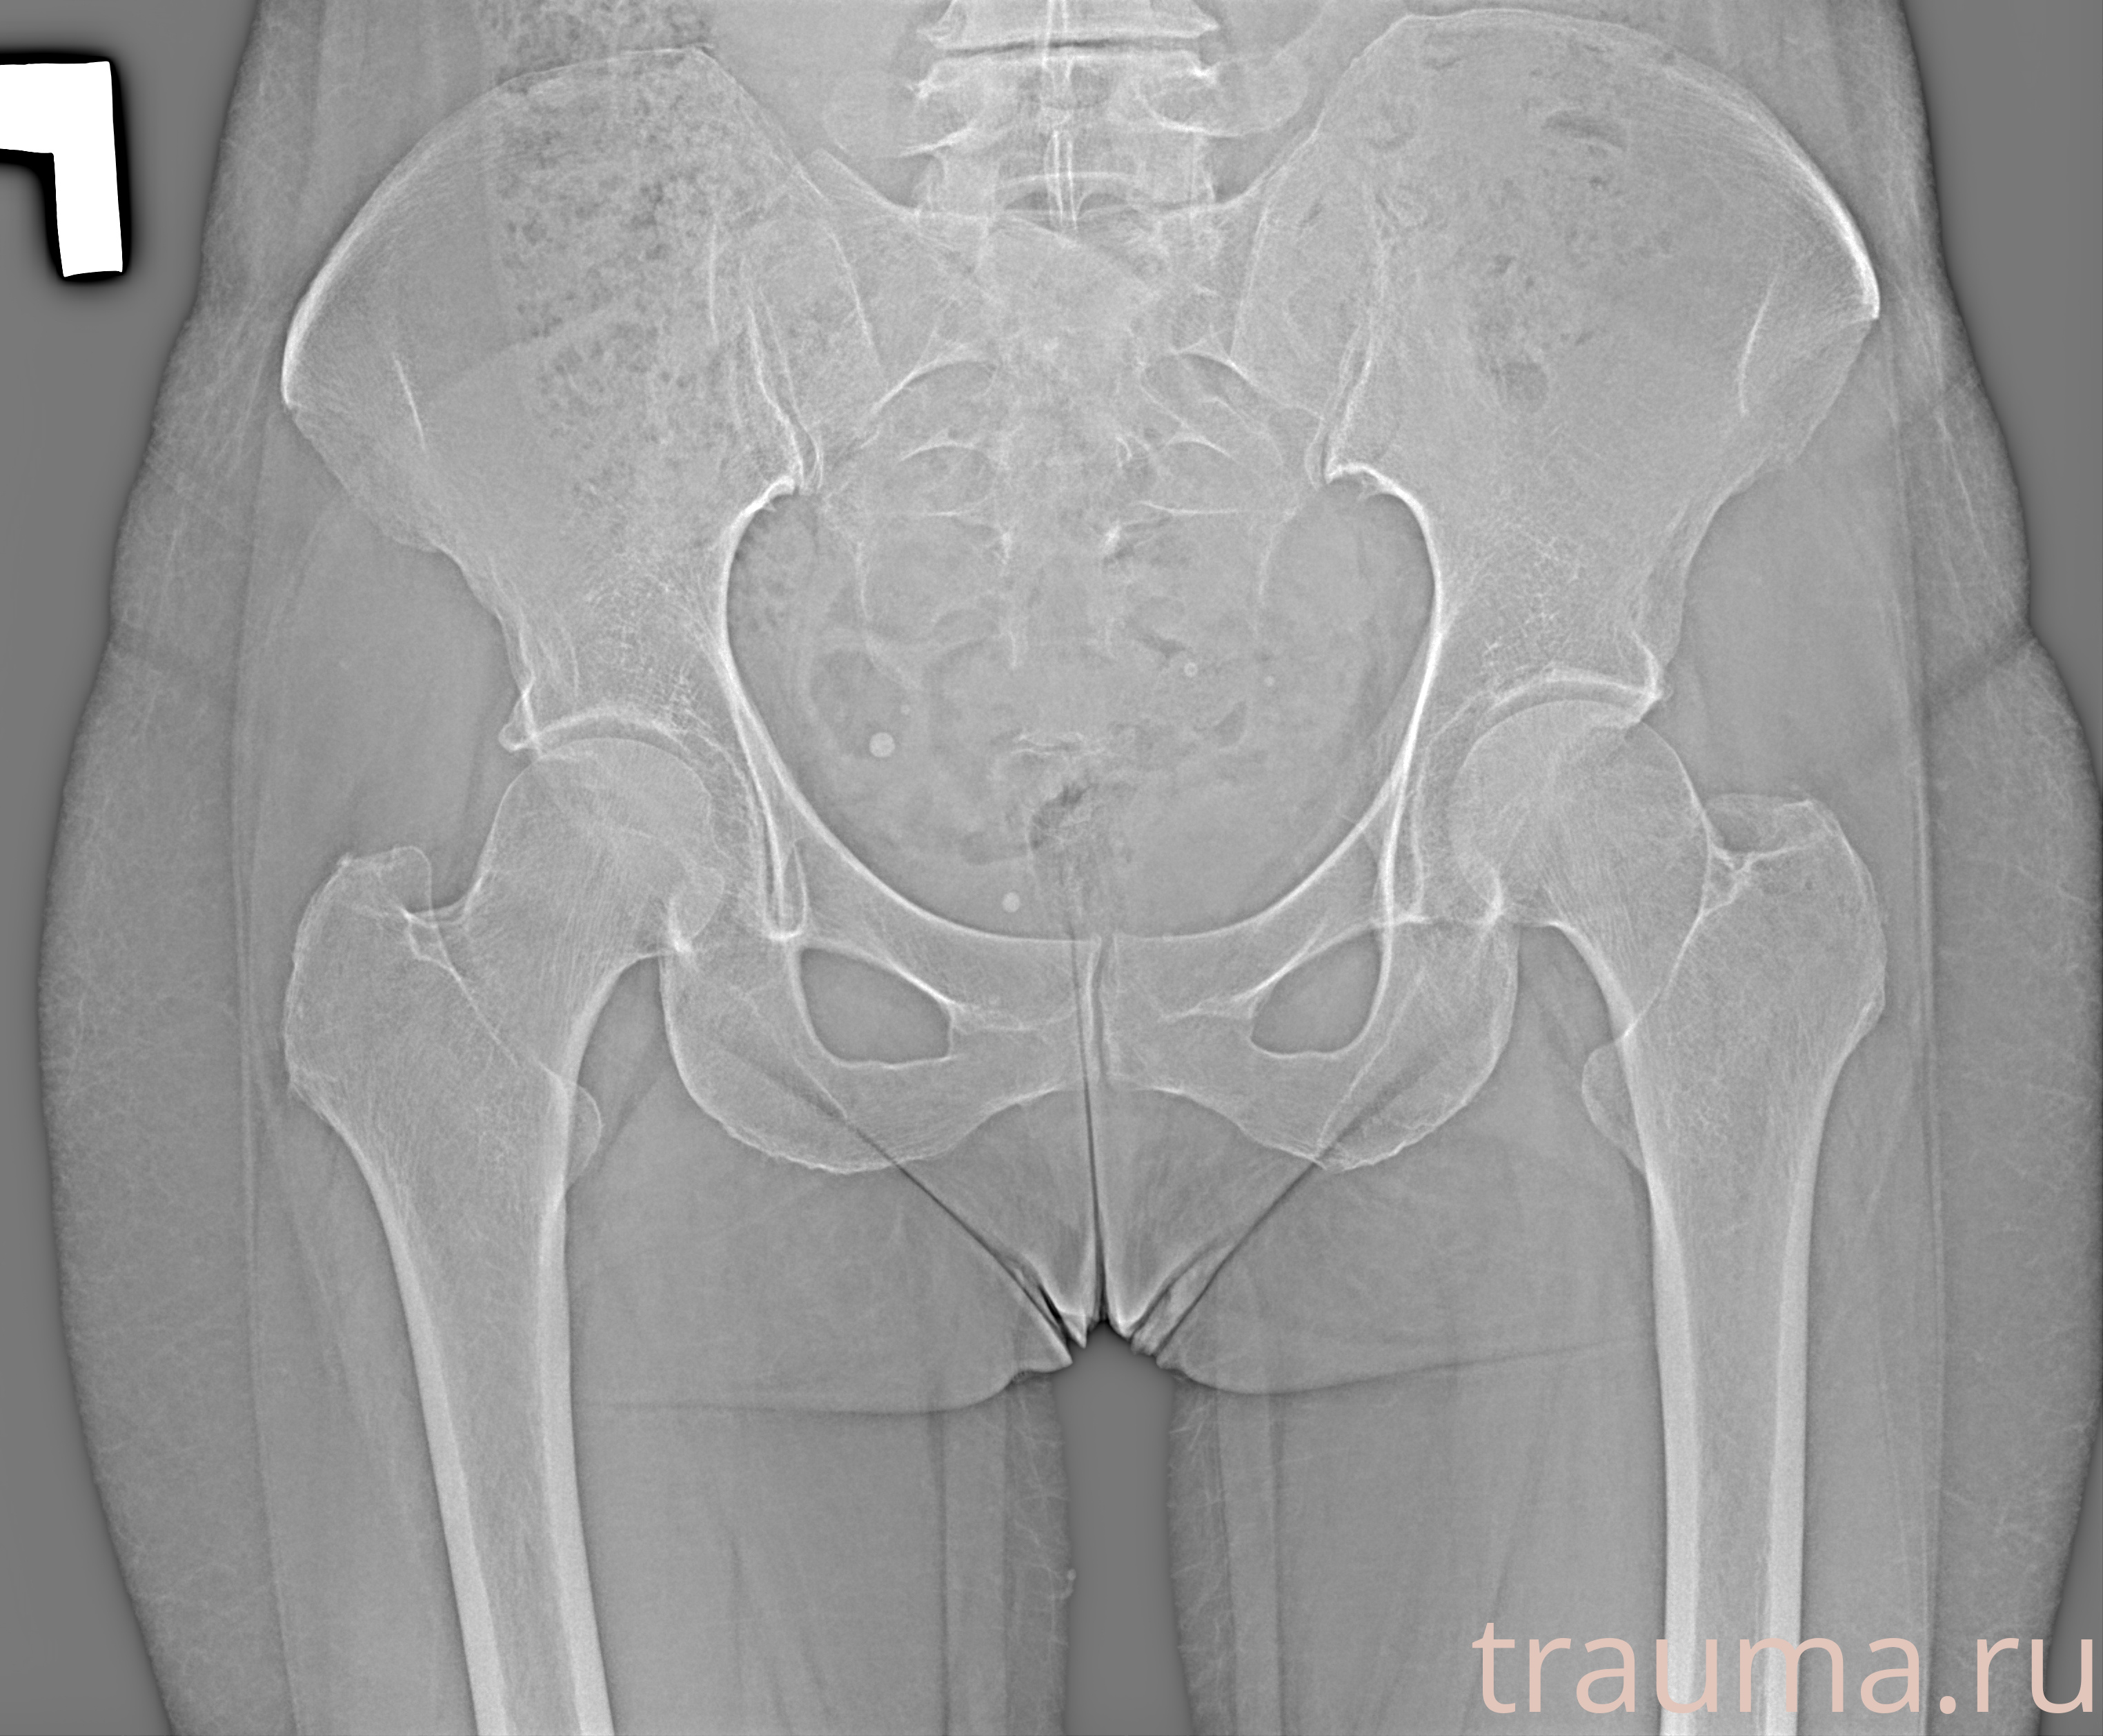

Рентгенограммы

Рентген на дому: по вашему адресу приезжает врач-рентгенолог, травматолог-ортопед с мобильным рентгеновским аппаратом, проводит диагностику травмы или заболевания, делает необходимые рентгенограммы, дает рекомендации по дальнейшему лечению. Получить качественные снимки в домашних условиях возможно благодаря уникальной методике, разработанной МосРентген Центром для института  Склифосовского